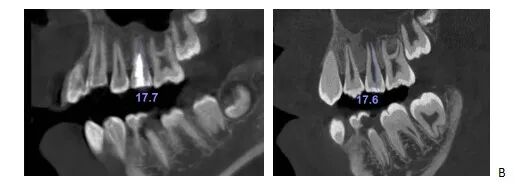

辅助检查:CBCT显示25牙根尖呈喇叭口样敞开,未发育完全,根尖低密度暗影。

CBCT矢状面显示25牙根尖未发育完成,根尖阴影